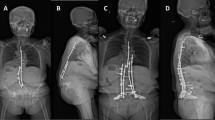

We heat-treated shape-memory alloy (SMA) rods to achieve a transition temperature between 34 and 47 °C and a C-shape austenite phase. We then developed a water-cooled generator capable of generating an alternating magnetic field (100 kHz) for induction heating. We next studied the efficacy of this system in vitro and determined some parameters prior to proceeding with animal experiments. We then employed a rabbit model, in which we fixed a straight rod along the spinous processes intraoperatively, and conducted induction heating postoperatively every 4 days for 1 month, while performing periodic X-ray assessments.

Significant kyphotic deformations with Cobb angles of about 45° (p < 0.01) were created in five rabbits, and no complications occurred throughout the experiment. The rabbits are still very much alive and do not show any signs of discomfort.